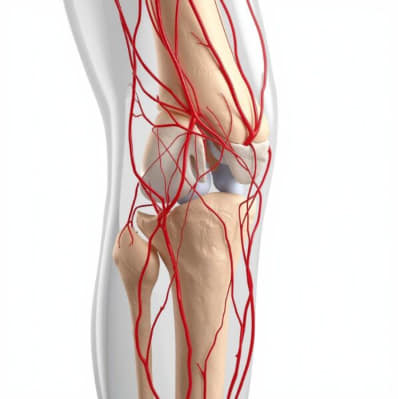

GAE is a novel, image-guided treatment developed to relieve chronic knee pain by blocking abnormal blood vessels in the joint. The procedure involves injecting tiny embolic agents—such as particles or coils—into specific genicular arteries, thereby reducing excess blood flow that fuels inflammation and pain.

In osteoarthritic joints, abnormal neovascularization—the formation of new, fragile blood vessels—plays a key role in inflammation and pain. GAE targets these vessels with precision:

- Step 1: Under angiographic guidance, the interventional radiologist maps the network of genicular arteries that supply the inflamed joint.

- Step 2: Embolic materials are introduced to selectively block these vessels.

- Step 3: Blood flow to the painful areas is reduced, leading to less inflammation and pain.

Why Anatomy Matters

Success depends heavily on the operator’s detailed knowledge of genicular artery anatomy, including its variations. Accurate targeting helps maximize efficacy and minimize risks like non-target embolization.